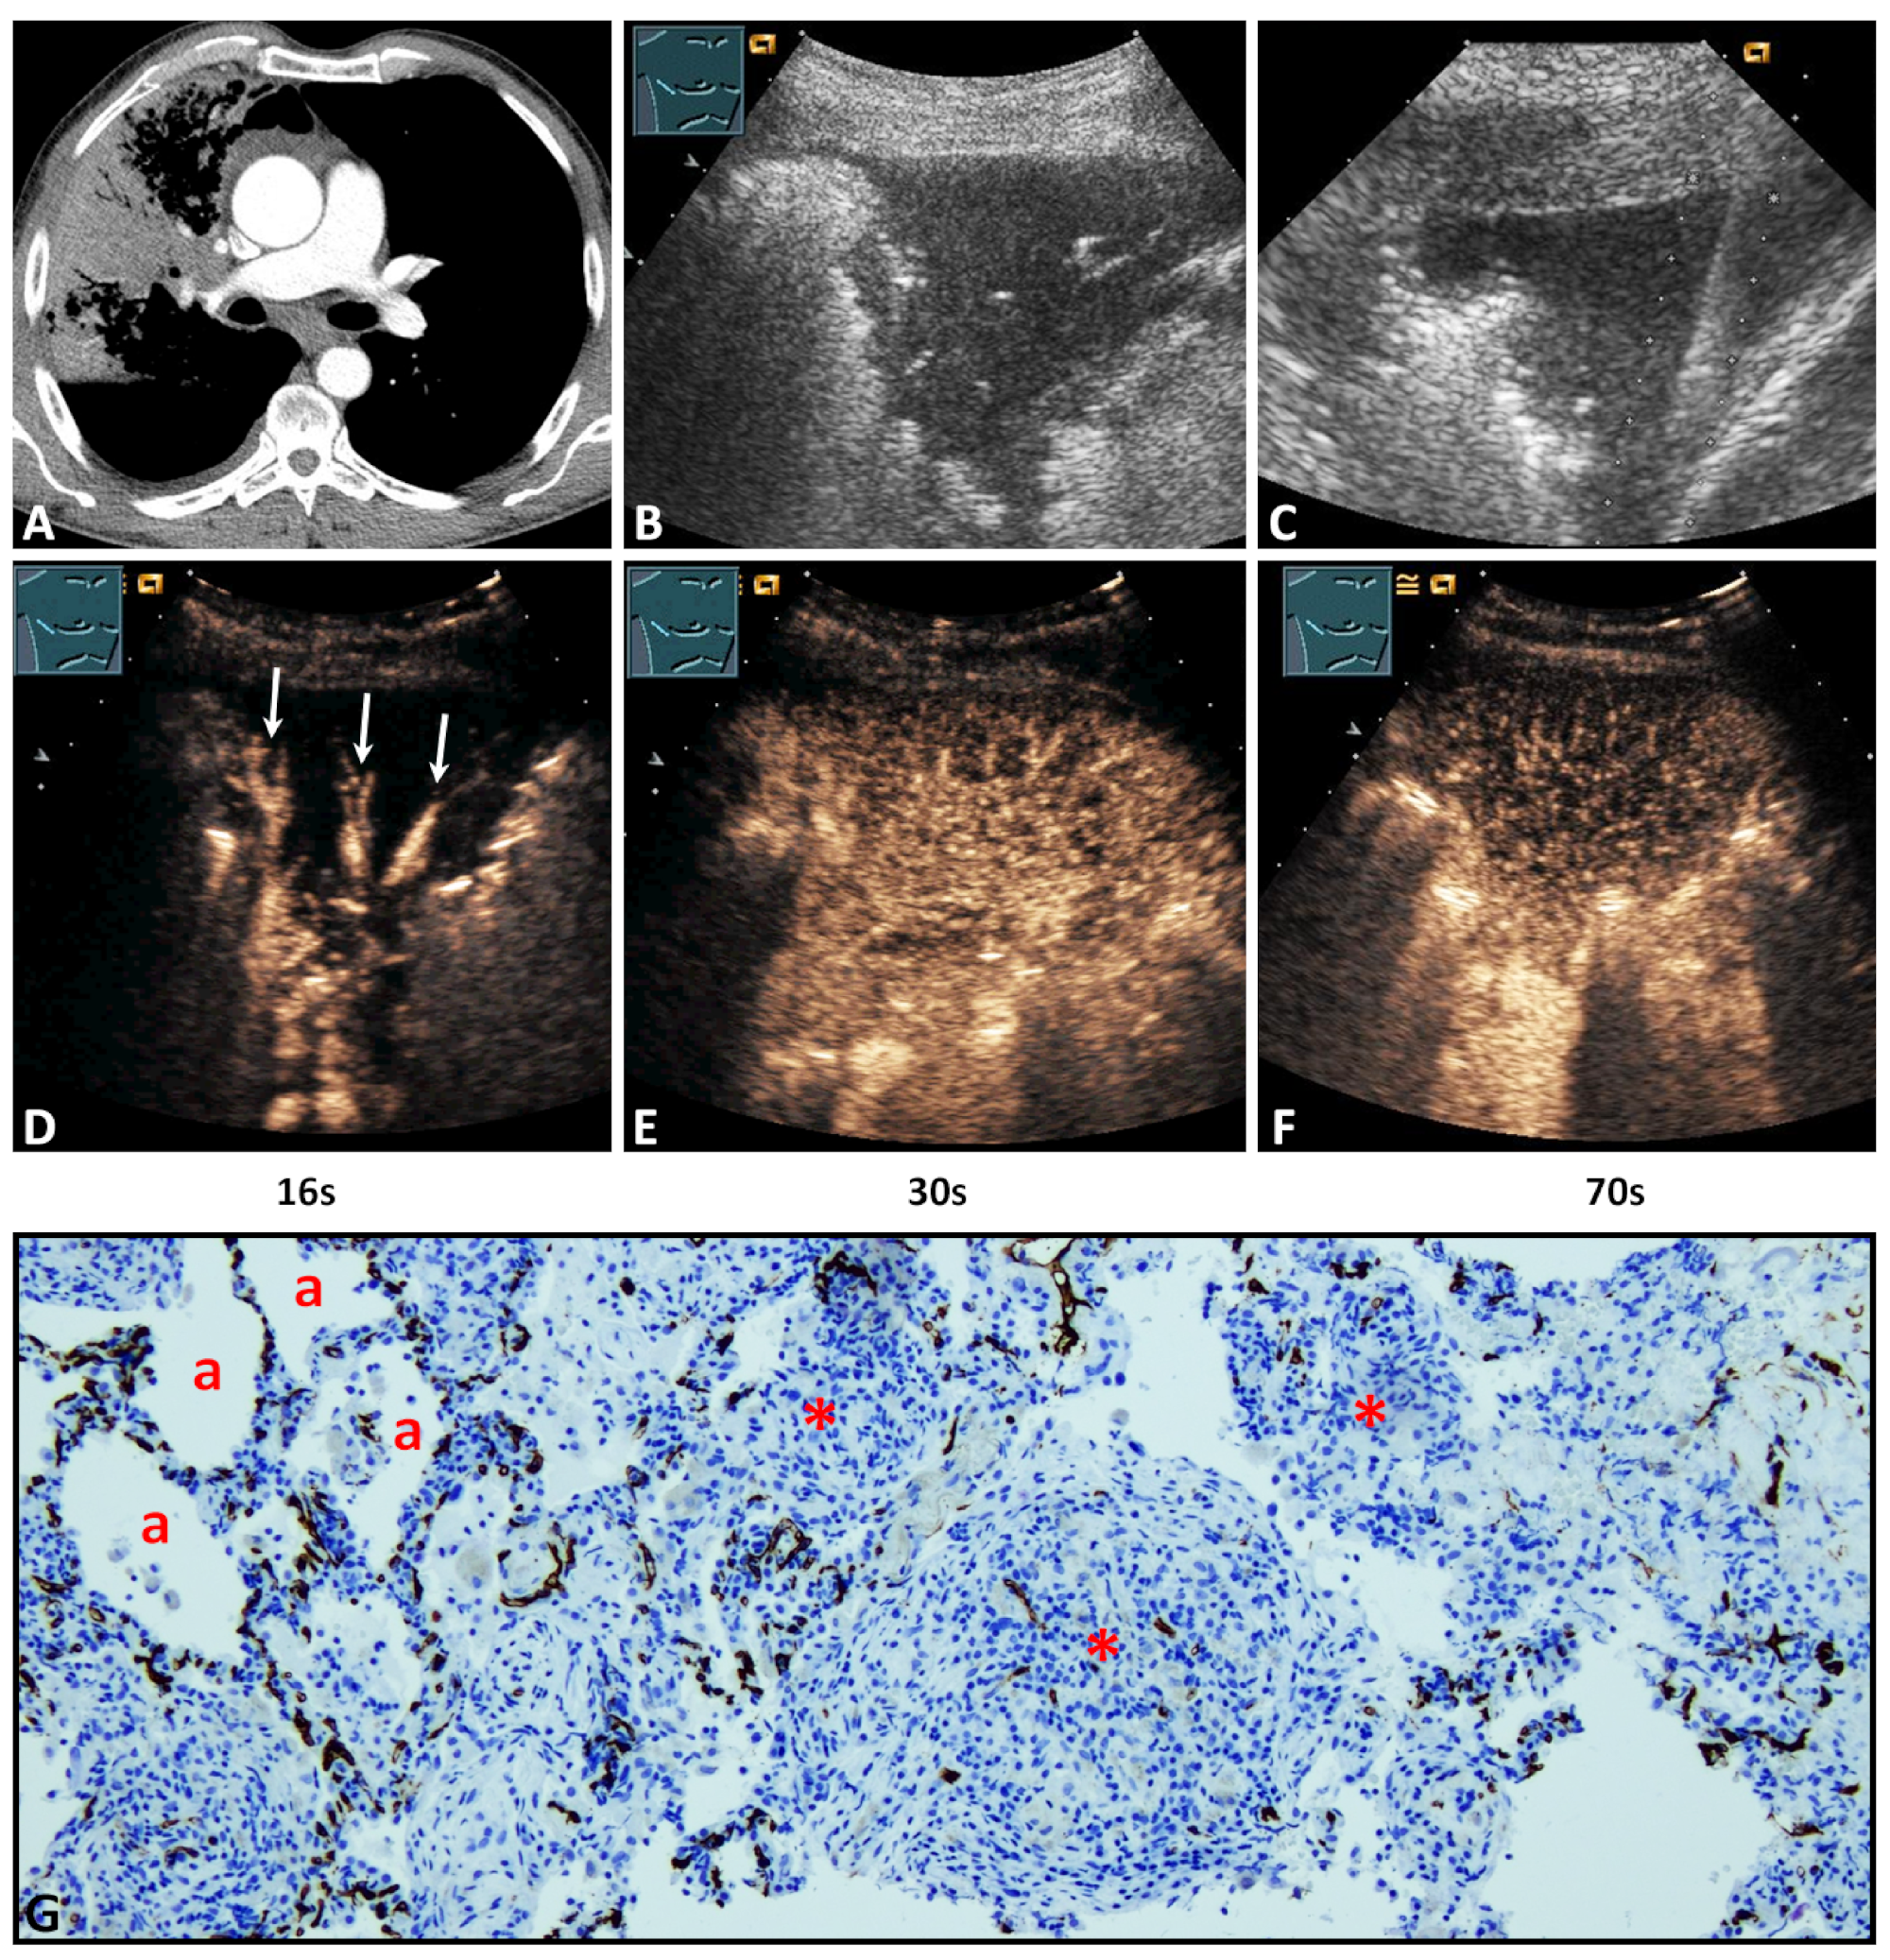

A 59-year-old male patient with lung consolidation on (A) computed tomography (courtesy of Prof. Dr. Andreas H. Mahnken, Department of Radiology, University Hospital Marburg) and (B) B-mode ultrasound. (C) An ultrasound-guided 18G-core needle biopsy of the lung lesion was performed. The histopathological examination of the lesion presents the diagnosis of organizing pneumonia. On contrast-enhanced ultrasound, the lesion showed (D) a pulmonary-arterial (arrows), (E) isoechoic, and homogenous pattern of enhancement (F) with an early decrease of enhancement. (G) In the tissue sample, immunohistochemical staining with CD34 was performed. To the left, preserved alveolar lung vasculature surrounding normal or macrophage-filled lung alveoli (a) is evident in favor of pattern A. On the right, reorganized lung tissue with fibrotic and granulating tissue with a high capillary density in a rather disorganized and chaotic pattern (*) is present, consistent with pattern B (×100).

Regarding TE, 27/38 lesions (71.1%) revealed a delayed enhancement due to BA perfusion (Figure 2D), and 11/38 lesions (28.9%) revealed an early enhancement due to PA perfusion (Figure 3D). Regarding EE, 29/38 cases (76.3%) revealed a marked enhancement (Figure 3E) and 9/38 cases (23.7%) a reduced enhancement (Figure 2E). Furthermore, 7/38 lesions (28.4%) showed a homogeneous arterial enhancement (Figure 3E), and 31/38 lesions (81.6%) showed an inhomogeneous arterial enhancement with evidence of NPAs on CEUS (Figure 2E). The DE (washout time) was rapid (<120 s) in 19/38 lesions (50.0%) and late (≥120 s) in 19/38 lesions (50.0%) (Figure 2F and Figure 3F).

3.4. Histopathological Data and Their Correlation with Contrast-Enhanced Ultrasound Pattern

All POPs were histologically confirmed to exclude malignancy. The histological confirmation was performed by ultrasound-guided biopsy in 25 cases (65.8%) (Figure 2C and Figure 3C) and by a thoracic surgical intervention in 13 cases (34.2%). The mean time difference between CEUS and histopathological sampling was 1.8 ± 1 weeks (range 1–4 weeks). A vascular pattern B similar to BA neoangiogenesis in lung tumors was found in all lesions (Figure 2G and Figure 3G). Moreover, in the 11/38 lung lesions (28.9%) that had a PA pattern of enhancement, the vascular pattern A similar to PA supply in healthy lung tissue [] or acute pneumonia [] was identified in addition to vascular pattern B (Figure 3G).

Regarding TE in this study, on CEUS, POPs had a predominantly (71.1%) delayed systemic enhancement in the arterial phase, indicating a BA supply. In all tissue samples, a disorganized and chaotic vascular pattern was seen (Figure 2) as evidence of BA neoangiogenesis [,]. Furthermore, in all lesions with a PA perfusion pattern of enhancement (28.9%), a regular alveolar vascular pattern was partially present in the corresponding tissue sample as an indication of PA supply (Figure 3) []. These findings indicate that, in the presence of a PA pattern of enhancement, a BA neoangiogenesis, as an important feature of chronic inflammatory and malignant processes, cannot be excluded by CEUS. In these lesions, early PA enhancement covered the delayed arrival of contrast medium via BA supply.

Regarding HE and EE, 81.6% of cases presented an inhomogeneous enhancement and 76.3% a marked arterial enhancement in comparison with splenic enhancement. Avascular areas (abscess, necrosis, hemorrhage), as a histopathological correlation to an inhomogeneous enhancement, were identified in 13/31 cases (41.9%). In the remaining cases, a histopathological correlation was not demonstrated, based on the fact that avital tissues were avoided in the biopsy or histopathological examination. All POPs with a PA pattern of enhancement showed a marked enhancement similar to other pathologies with PA supply, such as compression atelectasis and acute pneumonias [,,]. Furthermore, 18/27 lesions (66.7%) with a BA pattern of enhancement showed an isoenhancement that may be indicative of a marked neoangiogenesis [].